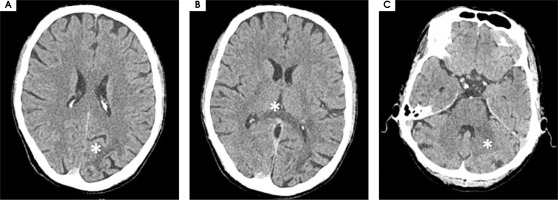

On February 27th, 2023 he was hospitalized in the neurological ward due to a sudden progression of sight loss to right homonymous hemianopsia. In the computed tomography (CT) scan hypodense lesions were found in the left parietal lobe, left middle cerebellar peduncle and the trunk of the corpus callosum. The lesion in the left parietal lobe was described as surrounded by vasogenic oedema (Figure I). The brain magnetic resonance imaging (MRI) with 1.5 Tesla scanner was performed and a nonenhancing lesion in the white matter of the left cerebellar hemisphere was reported along with the signs of restricted diffusion. The images suggested an acute ischemia. Similar lesions were also found in subcortical and periventricular white matter of left parietal lobe (Figure II).

Figure I

Computed tomography axial scans showing hypodense lesions in (A) left parietal lobe, (B) trunk of corpus callosum (white star), (C) left middle cerebellar peduncle (white star)

The results of a CT scan were comparable with those performed in February.